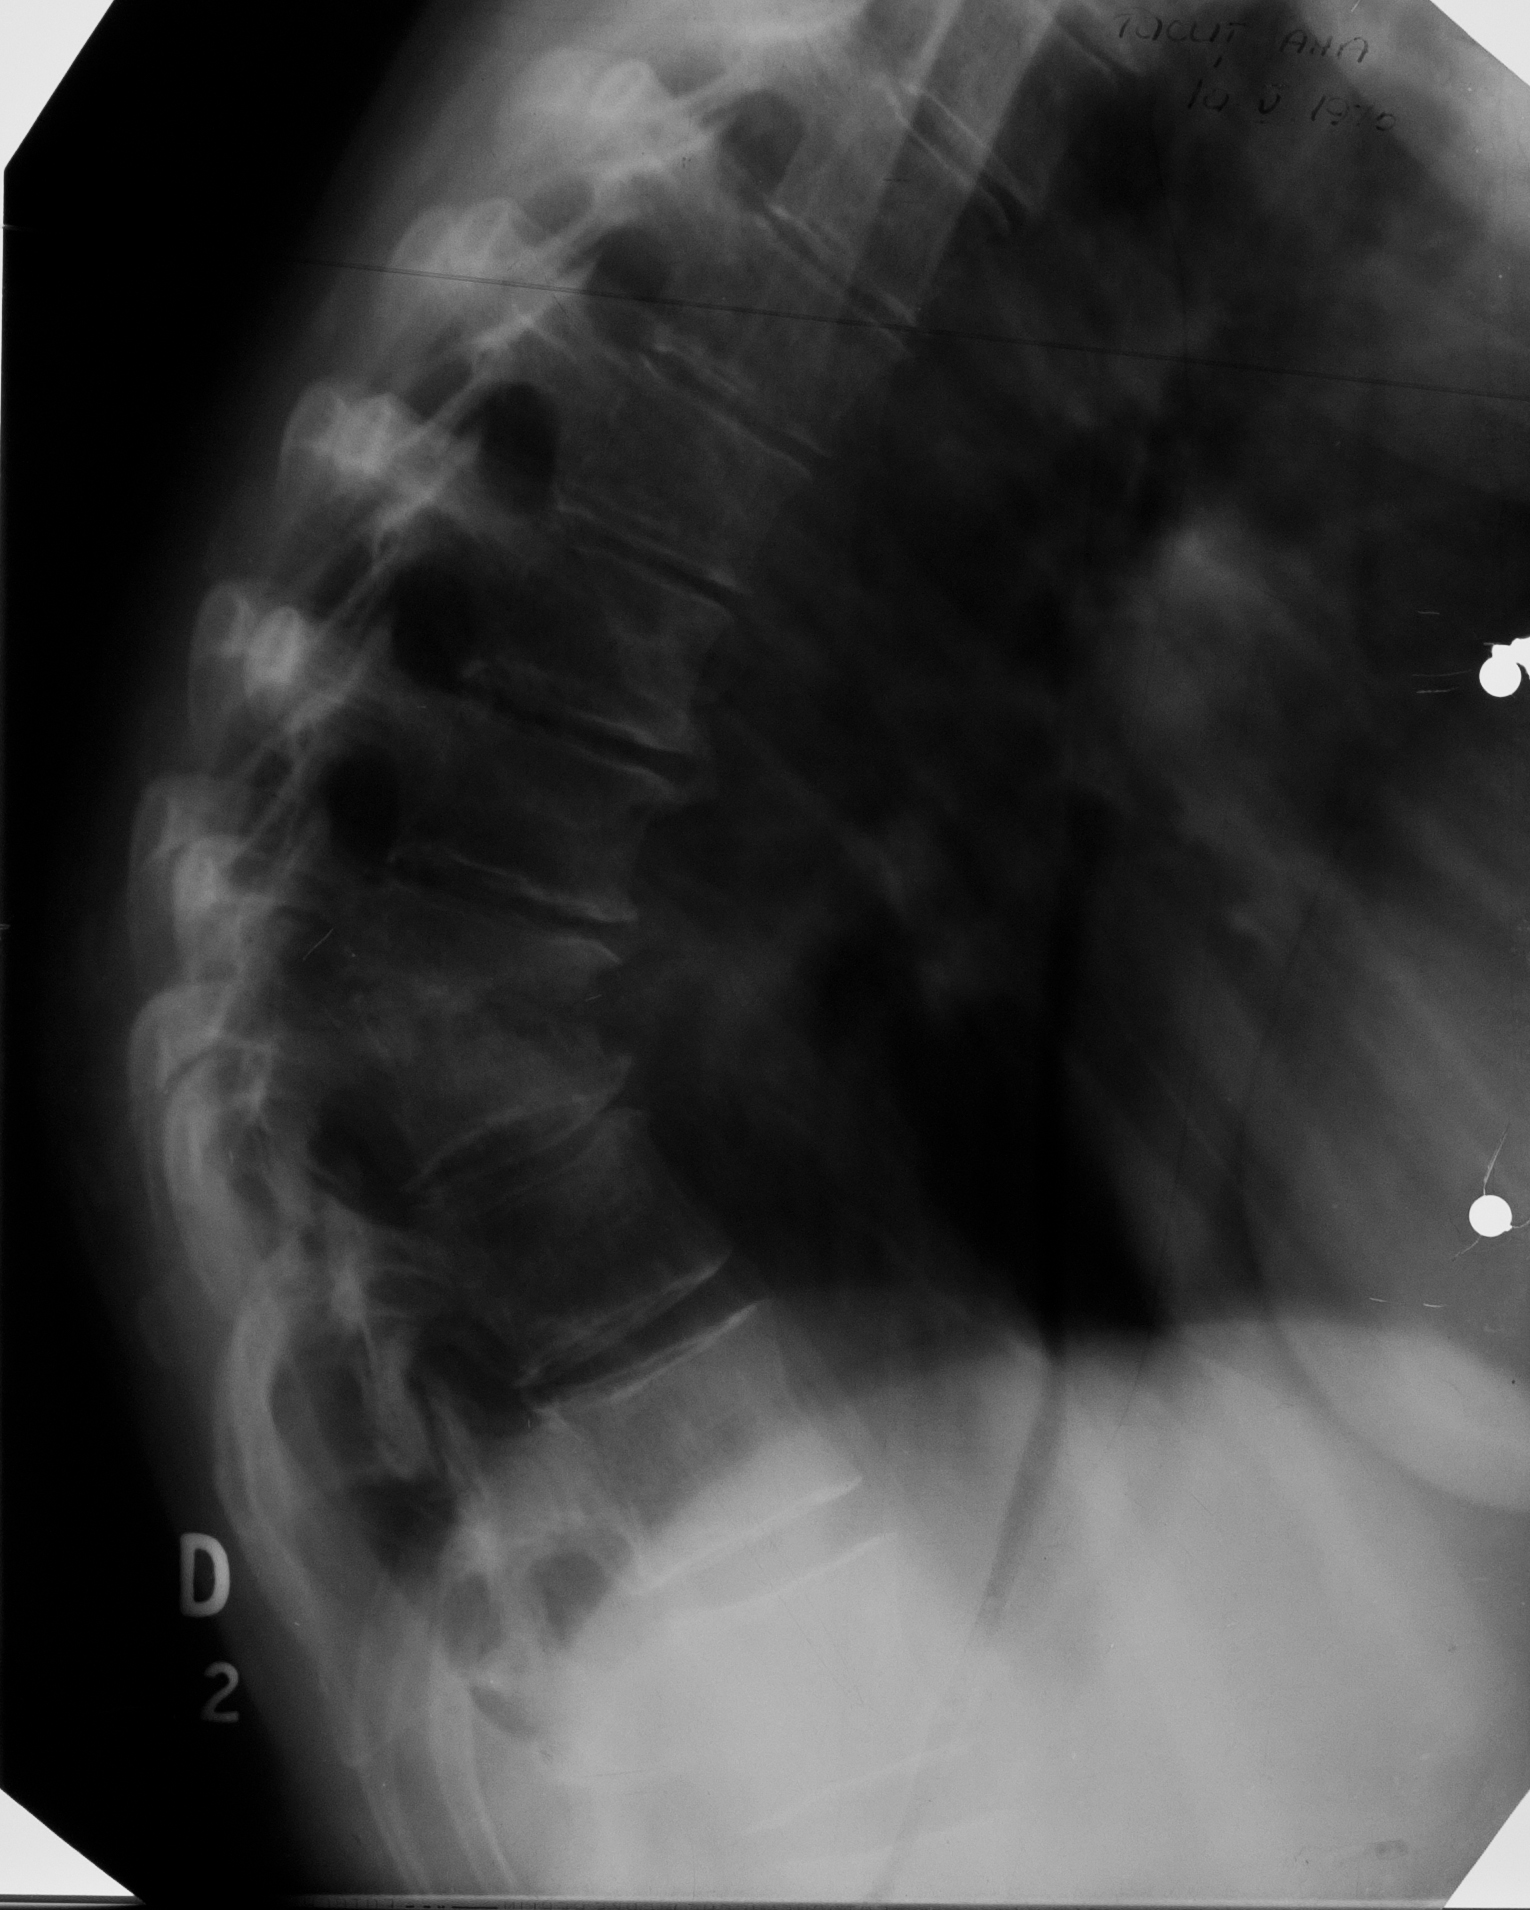

Osteoartrita TBC la nivelul coloanei vertebrale

Radiografie de coloana toracala, se vad 2 corpuri vertebrale cu spatial dintre ele absent, ele de dimensiuni mai reduse decat normal cu suprafete articulare neregulate, iar adiacent opacitate fusiforma

!!! Se cheama: Morbul lui Bot, (umflatura de pe margine e fusul Botic)

OSTEOARTRITĂ TBC

Accentuarea cifozei dorsale, nu e rotunda ci unghiulara, datorata distructiei unor corpuri vertebrale (lizei acestora), ramanând niste resturi care s-au sudat partial si au facut un bloc vertebral botic

CIFOZĂ ÎN URMA TUBERCULOZEI VERTEBRALE